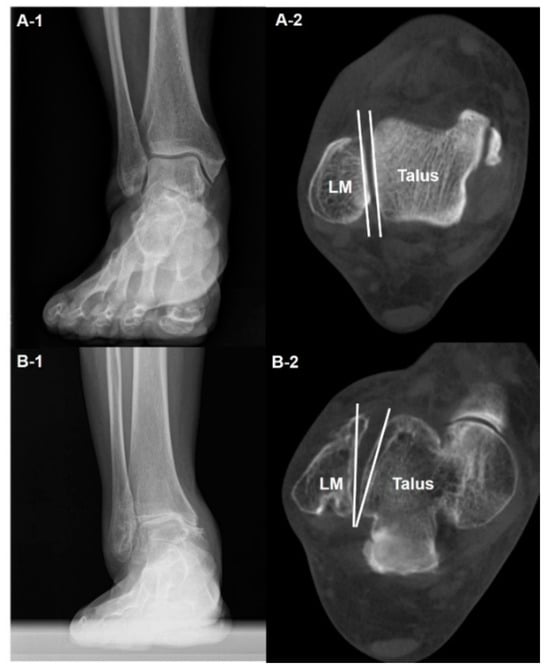

- Kim, J.B.; Yi, Y.; Kim, J.Y.; Cho, J.H.; Kwon, M.S.; Choi, S.H.; Lee, W.C. Weight-bearing computed tomography findings in varus ankle osteoarthritis: Abnormal internal rotation of the talus in the axial plane. Skelet. Radiol. 2017, 46, 1071–1080. [Google Scholar] [CrossRef]